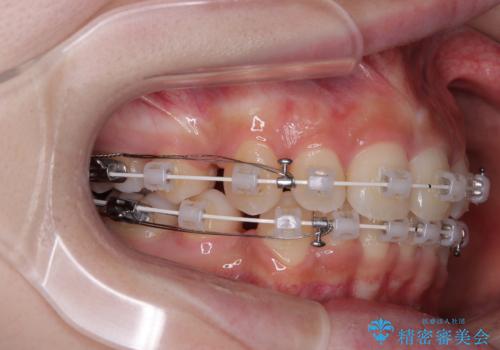

- 矯正装置

- 審美装置

- 2年11ヶ月

- 30回以上